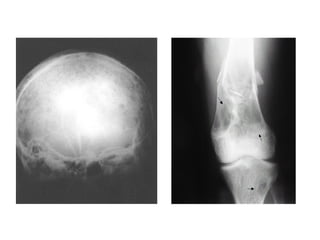

Hematoma Epidural

Ossos e Articulações

● Hemartroses

● Dor óssea

● Edema articular

Hematoma e hemartrose